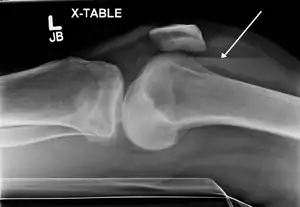

| Lipohemarthrosis (blood and fat in the joint space) seen in a person with a subtle tibial plateau fracture. The arrow indicates a fluid level between the upper fat component and the lower blood component. | |

X-ray of Hemarthrosis